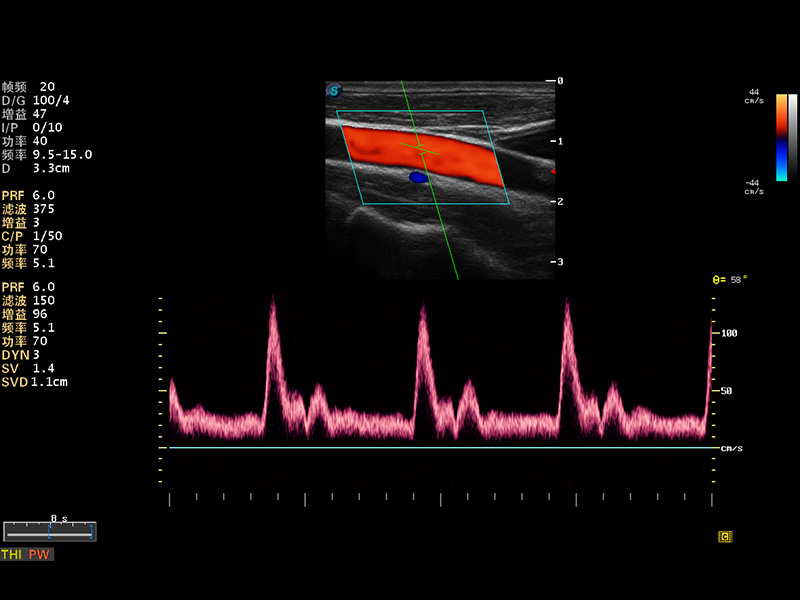

S8 EXP便携式彩色多普勒超声诊断仪是1xBET研发的高端全身应用型便携彩超。高通道的VIS平台融合可视化(Visual)、智能化(Intelligent)和人性化(Smart)的特点,配以1xBET自主研发生产的探头大家族,使您能够快速、准确的获得病人信息,提高工作效率的同时减轻疲劳。

多波束形成器